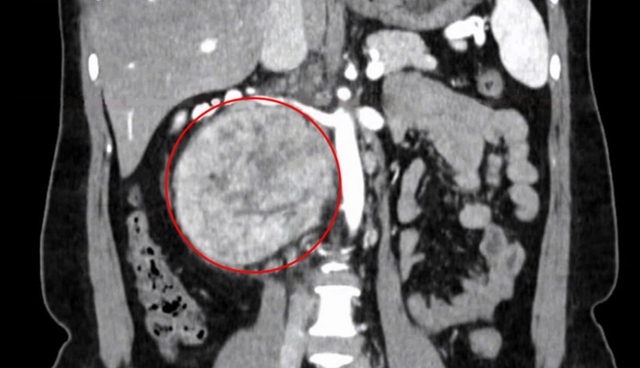

2 tuần trước, chị Ngà đến Bệnh viện Đa khoa Tâm Anh TP.HCM khám sức khỏe tổng quát, kết quả chụp cắt lớp vi tính (CT Scan) vùng bụng phát hiện một khối u rất lớn ở vùng sau phúc mạc – là những khối u bất thường xuất hiện giữa khoang ổ bụng và cột sống lưng, thường phát sinh từ mô, thần kinh, tế bào mầm hoặc các nang sau phúc mạc.

Khối u “khổng lồ” sau phúc mạc. Ảnh: BVCC

“Khối u rất lớn, kích thước 12 cm nằm sau tĩnh mạch chủ, cạnh động mạch và hai tĩnh mạch thận, gây chèn ép các cơ quan lân cận, chúng tôi phải tiến hành mổ mở để lấy trọn khối u một cách tốt nhất cho người bệnh”, TS.BS Nguyễn Hoàng Đức, Trưởng khoa Tiết niệu, Trung tâm Tiết niệu – Thận học – Nam khoa cho biết.